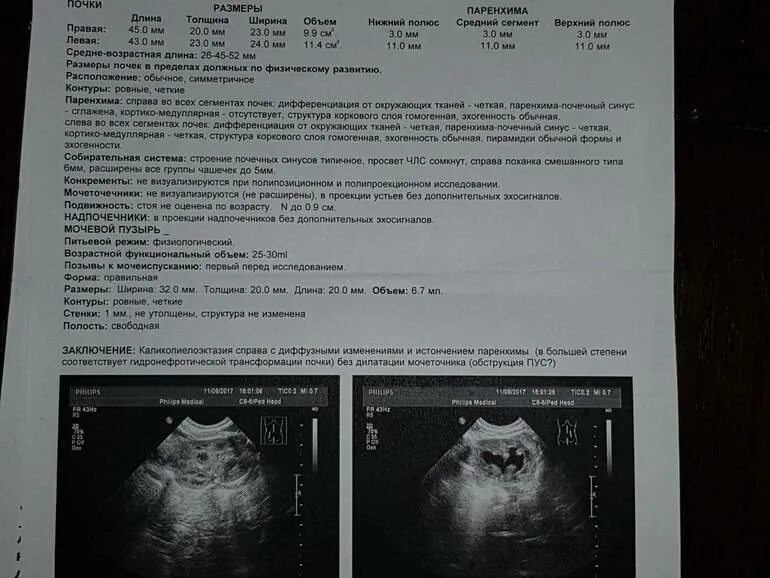

Узи сердца узи почек